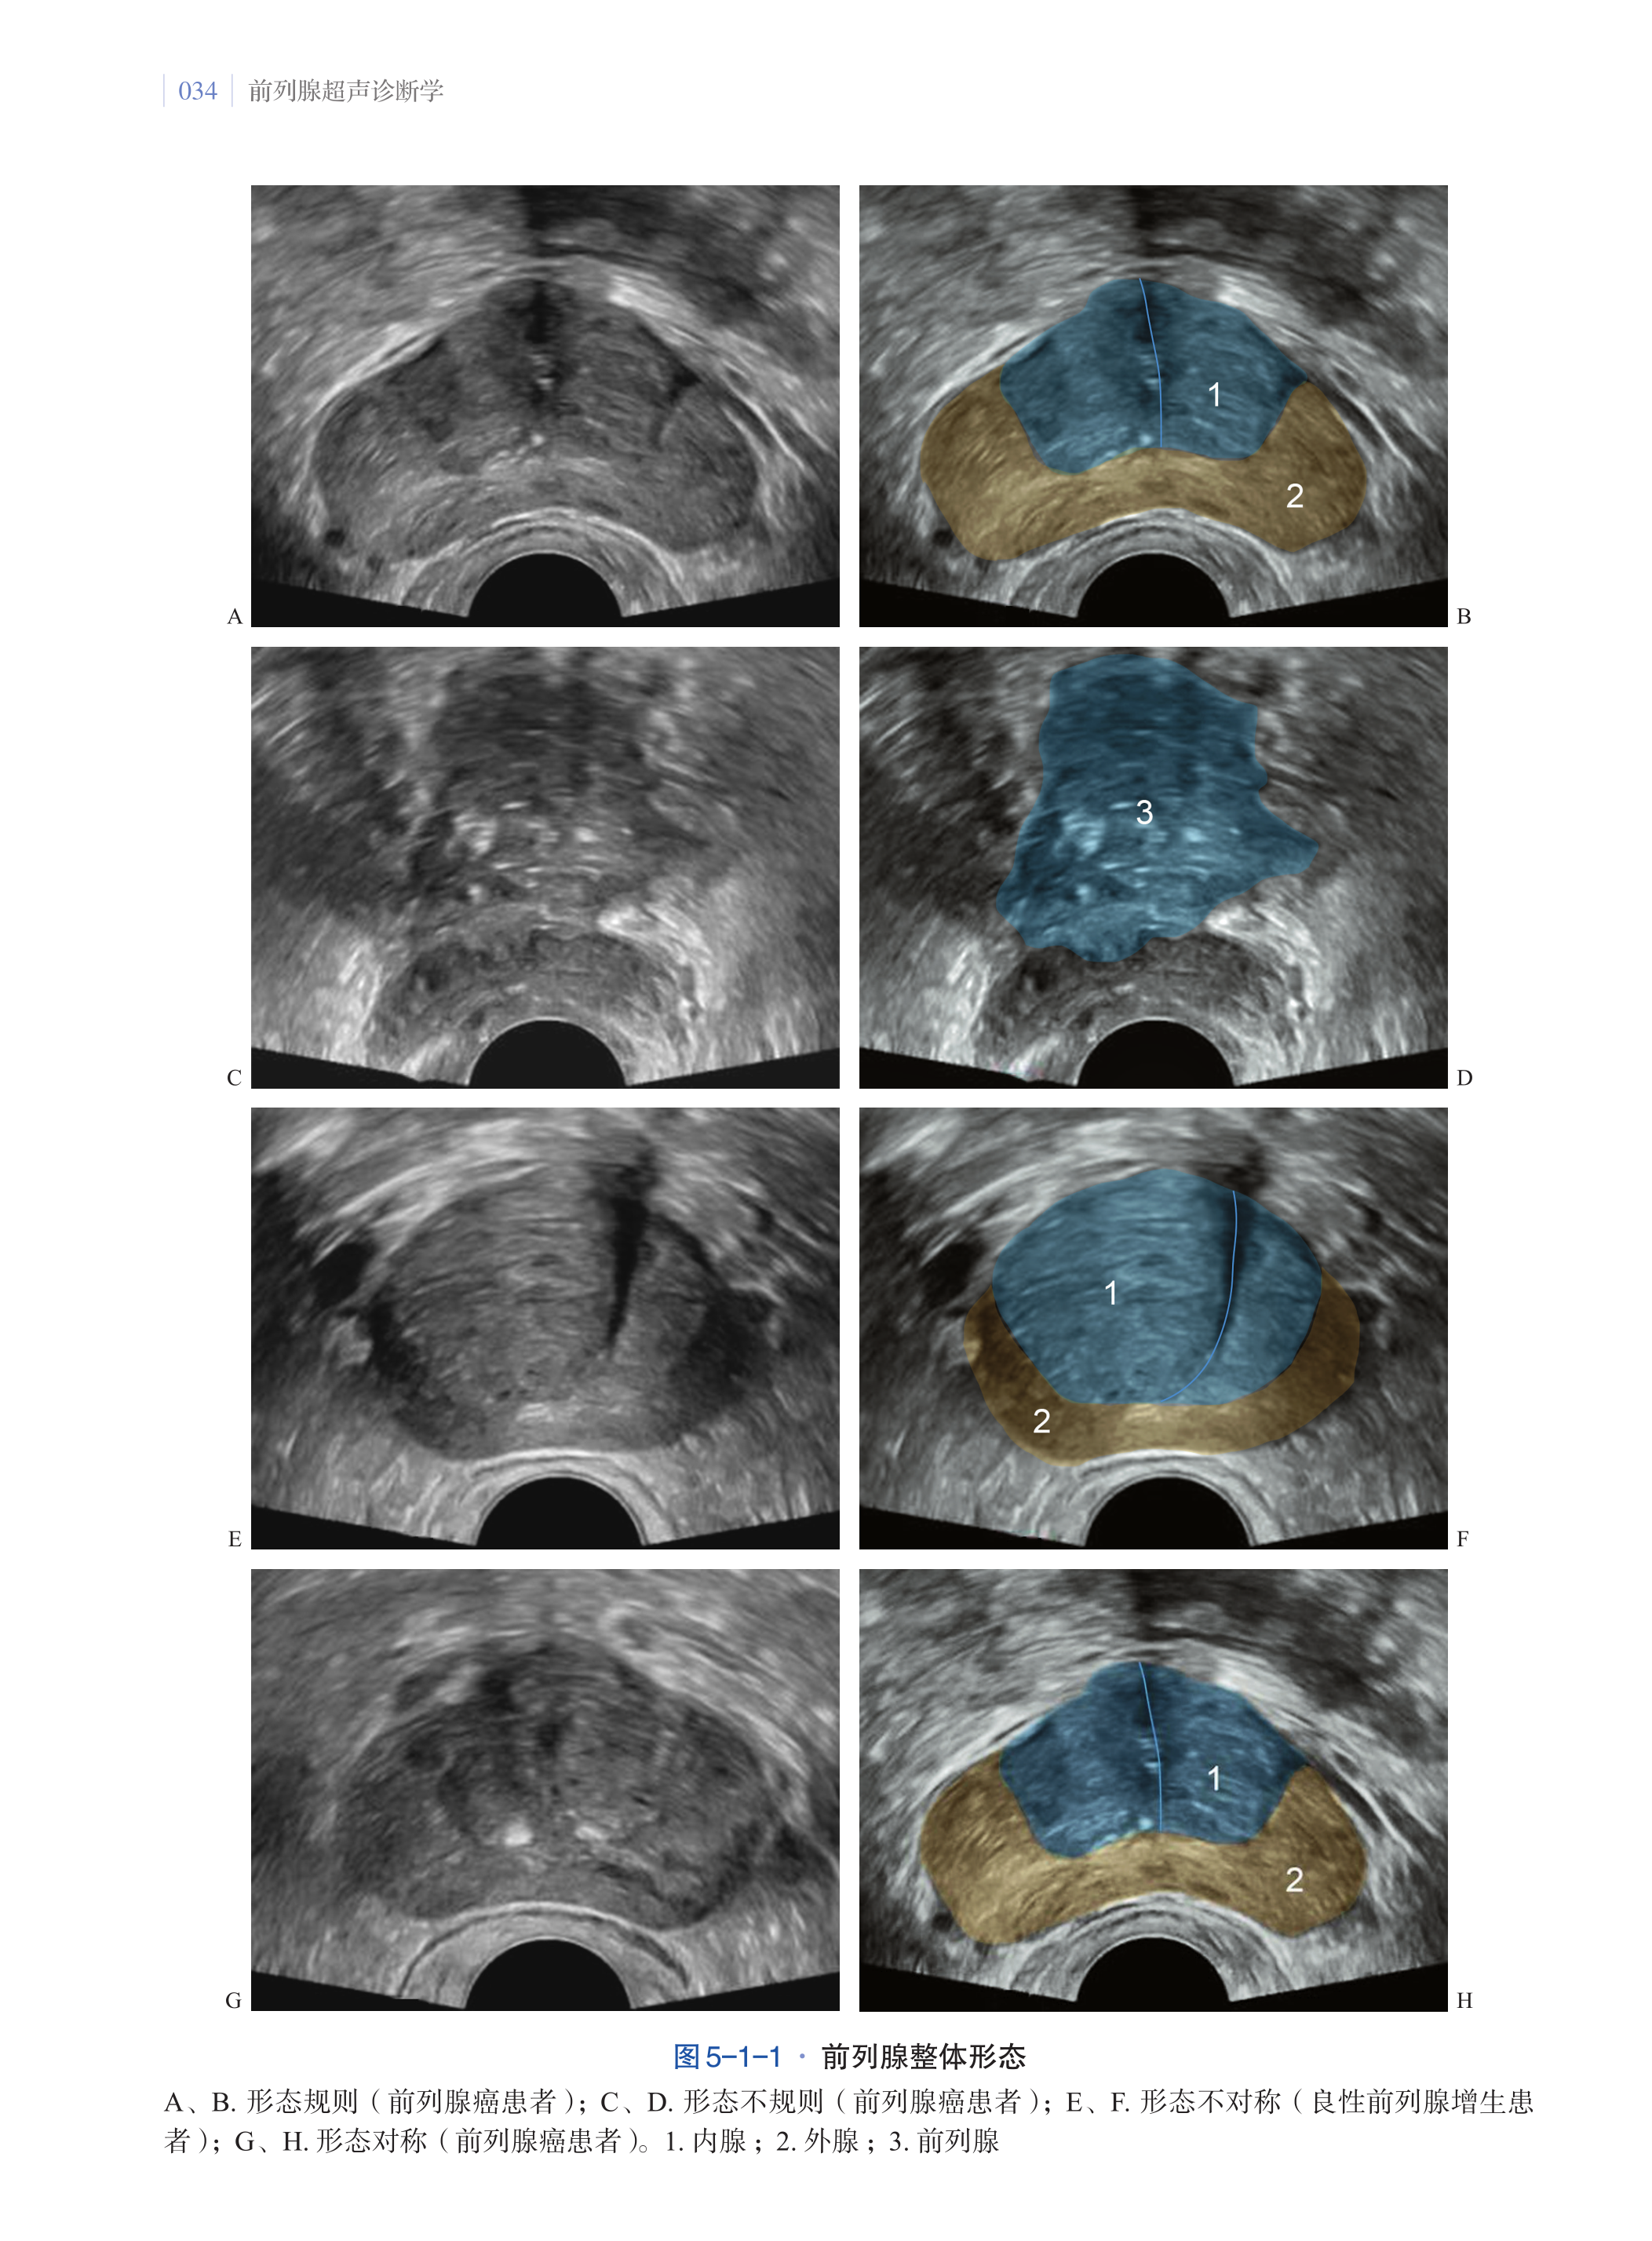

第五章·前列腺超声图像解读及伪像 033

第一节·前列腺超声图像解读 033